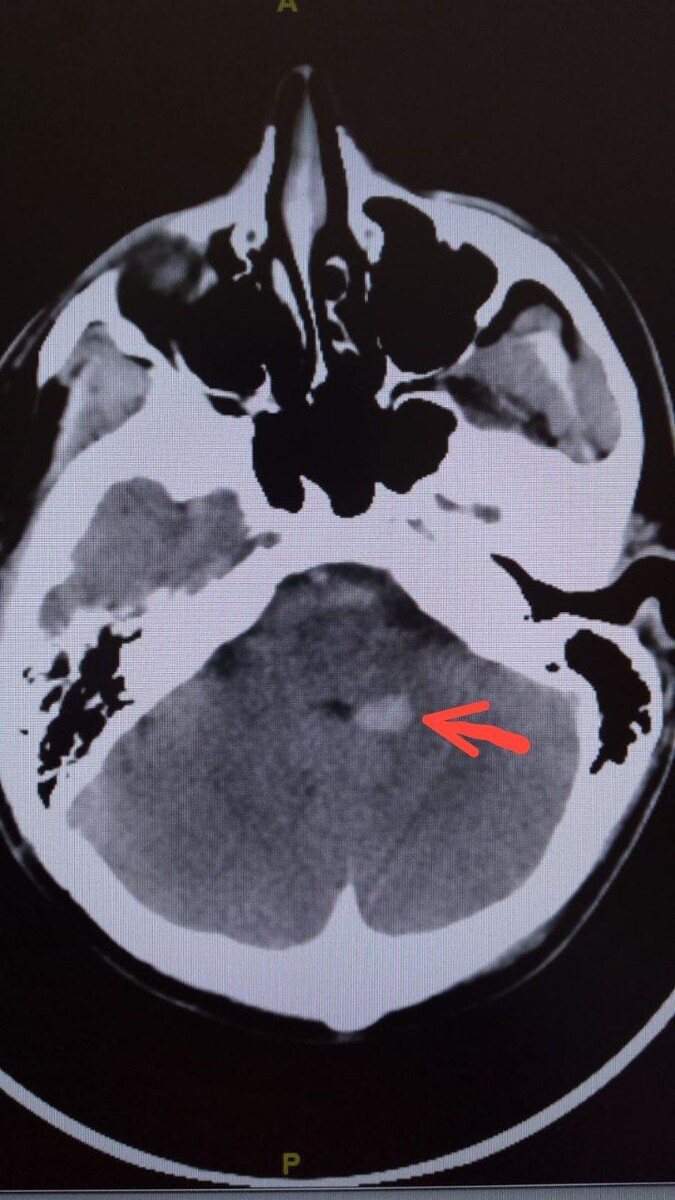

Мозжечковые пробы пациент тоже выполнял. Пробу Ромберга, разве что, было не оценить, ввиду выраженного головокружения и тошноты со рвотой. Кроме горизонтального нистагма 3 ст. , не стихающего, не было в неврологическом статусе иных отклонений. Пациент был направлен на СКТ головного мозга в экстренном порядке, где нашли зону кровоизлияния в левых ножках мозжечка (срез КТ прикрепил)